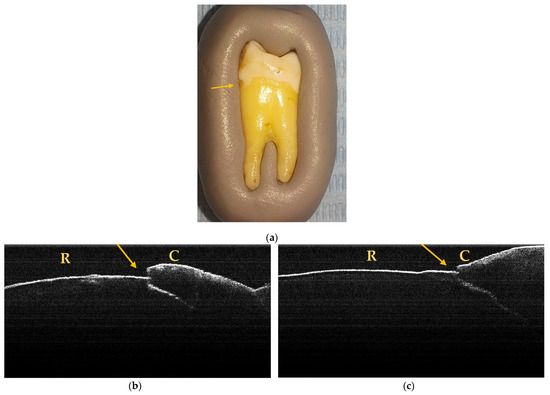

Through macroscopic and OCT examination, 34 NCCLs were identified, of which 14 were in incisors (41.18%) and 20 in premolars (58.82%). It was observed that, in the end, 6 teeth (1 incisor and 5 premolars) presented several NCCLs that were visible macroscopically and on OCT examination (Figure 6).

Figure 6.

Macroscopic and OCT aspects of PM6: (a) macroscopic image showing superficial NCCL on the buccal surface, indicated by the arrow; (b) OCT image of the buccal surface where an NCCL is observed, indicated by the arrow; (c) OCT image of the mesial surface where an NCCL is observed, indicated by the arrow.